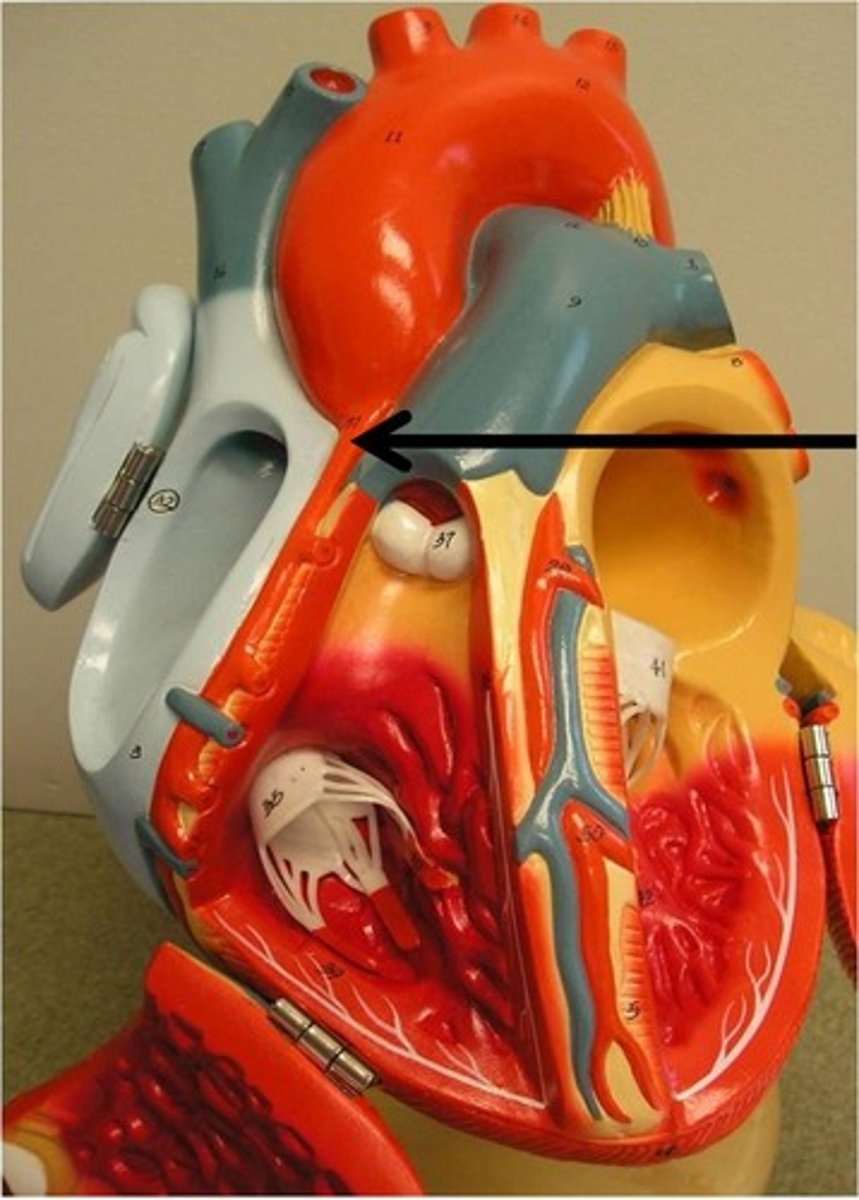

ascending aorta

branches include right and left coronary arteries

right coronary artery

left coronary artery

aortic arch

superior vena cava

inferior vena cava